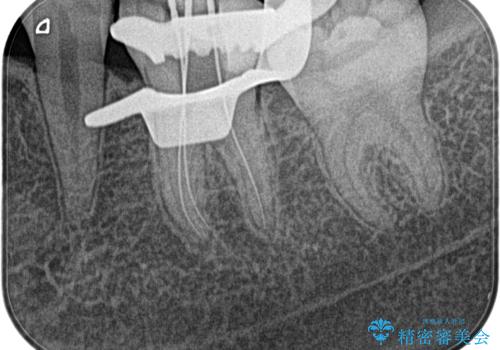

- 奥歯がズキズキ痛いことを主訴に来院されました。

検査の結果、診断を症候性不可逆性歯髄炎、症候性根尖性歯周炎とし抜髄を行っております。

根管充填はCWCT。

根管形成はマルテンサイト相を有するNi-TIロータリーファイル(NEX MS) 使用。